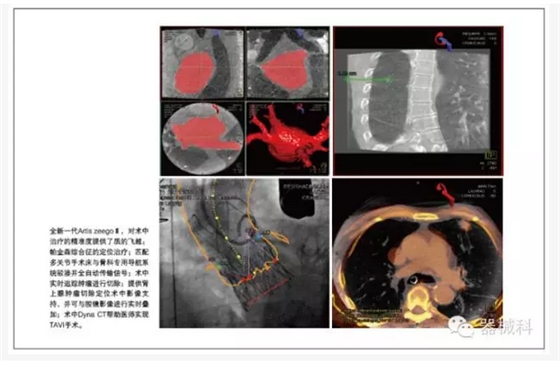

胸心外科是復(fù)合手術(shù)室的最重要使用科室之一。西門子在中國(guó),在世界,都是心臟復(fù)合手術(shù)室技術(shù)的開(kāi)創(chuàng)者和領(lǐng)先保持者。國(guó)內(nèi)著名的心血管病中心一直采用西門子復(fù)合手術(shù)室,并開(kāi)創(chuàng)了心臟外科復(fù)合手術(shù)的“中國(guó)式經(jīng)驗(yàn)”。在TAVI等治療上,西門子擁有獨(dú)特的軟硬件支持,特別是術(shù)中Dyna CT,可以幫助醫(yī)師實(shí)現(xiàn)TAVI手術(shù)。

在胸外科肺部腫瘤及肝臟腫瘤微創(chuàng)手術(shù)的治療最前沿,西門子復(fù)合手術(shù)室提供術(shù)中腫瘤定位等實(shí)用技術(shù)支持,通過(guò)實(shí)時(shí)的Dyna CT和術(shù)前MR圖像融合,包括超聲及術(shù)中腔鏡影像,來(lái)確定腫瘤的位置,并術(shù)中實(shí)時(shí)追蹤腫瘤進(jìn)行切除。

在骨科領(lǐng)域,Artis zeego與傳統(tǒng)小C臂相比,劑量低,影像更清晰,并可提供特殊體位的3維重建和清晰的CT影像,巨大的投照面積,可提供全髖,肩關(guān)節(jié),全胸椎,全腰椎的一次成像,機(jī)器人提供的靈活投照角度,且具備投照記憶功能,大幅減少了術(shù)中劑量,縮短了手術(shù)時(shí)間;而且機(jī)器人可匹配多關(guān)節(jié)手術(shù)床與骨科專用導(dǎo)航系統(tǒng)駁接并全自動(dòng)傳輸信號(hào)。

特別是術(shù)中實(shí)時(shí)的CT評(píng)估,對(duì)于術(shù)中治療的精準(zhǔn)度提供了質(zhì)的飛越。其實(shí),對(duì)于全新一代Artis zeegoⅢ,他的神奇還包括6秒360度極速旋轉(zhuǎn)采集,十字繡激光定位引導(dǎo)穿刺,多臟器的iFlow血流編碼及PBV功能成像。以及我們和內(nèi)鏡微創(chuàng)界的達(dá)芬奇機(jī)器人強(qiáng)強(qiáng)聯(lián)合,開(kāi)展更尖端復(fù)雜的精準(zhǔn)微創(chuàng)手術(shù)。